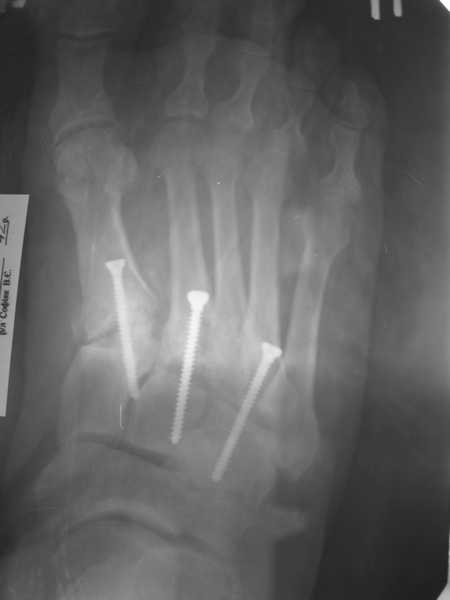

Здравствуйте , уважаемые коллеги. Обратился пациент, мужчина 42лет. для дальнейшего

лечения. Травма 11.09., ДТП.

15.09 проведено оперативное лечение (Блокирующий стержень левого

бедра - статическая система. Открытое вправление вывиха в суставе

Лисфранка и фиксация мет. фиксаторами.)

2. О суставе Лисфранка...

По суставу Лисфранка : 1- 8 -9 нед . полный покой в гипсовой шине,а

потом дозированная нагрузка. 2- Сейчас (на 7 нед.) пригипсовать

каблук под пятку и давать дозированную нагрузку, и на 12 нед,

Собственно такая фиксация сустава после вывизи никакой гипсовой иммбилизации не подразумевает! Через 6 недель винты можно удалять и разрешать полную нагрузку.... Прошло уже 7 недель, на сколько я понял, .....

Резюме: Удаляйте сейчас винты из стопы, динамизируйте стержень на бедре..Дайте нагрузку... Обсудите с больным вероятность и необходимость возможной реоперации на бедре, не дожидаясь таких осложнений как несращение, рефрактура и/или перелом штифта...